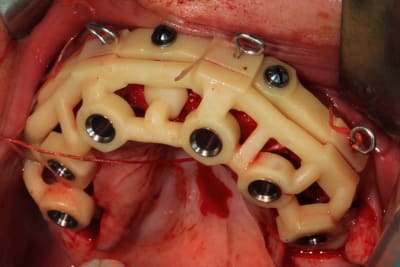

hors sujet, mais en regardant dans mes dossiers pour mettre les photos de guide, je retrouve celui-ci.

Bi-max faite il y a quelques années. Patient anti-vax, décédé du covid il y a 4 mois...

c est un guide coulé ? en titane ?

c'est dommage que jeff ne poursuive pas la discussion... Hokusai voici le patient qui a bénéficié de ce guide en début de chirurgie (22)

Pourquoi penses tu que le guide est en titane ?

parce qu il est en contact avec l os... alors je me dis qu il doit etre en titane.

mais en meme temps je pense qu il a ete imprime en resine calcinable puis mis en moufle pour être coulé... et que c est chaud de couler du titane.

alors peut etre est il coulé en crco...

je me questionne ;)

En effet le titane coulé c'est très compliqué, j'ai coulé le guide que présente jeff (23) en Cobalt-chrome

non, le chrome cobalt est très résistant, je n'ai jamais eu de casse avec mes guides ajourés. Ils offrent une bonne visibilité contrairement au guide à étage en plastique comme tu peux l'observer avec celui de jeff.